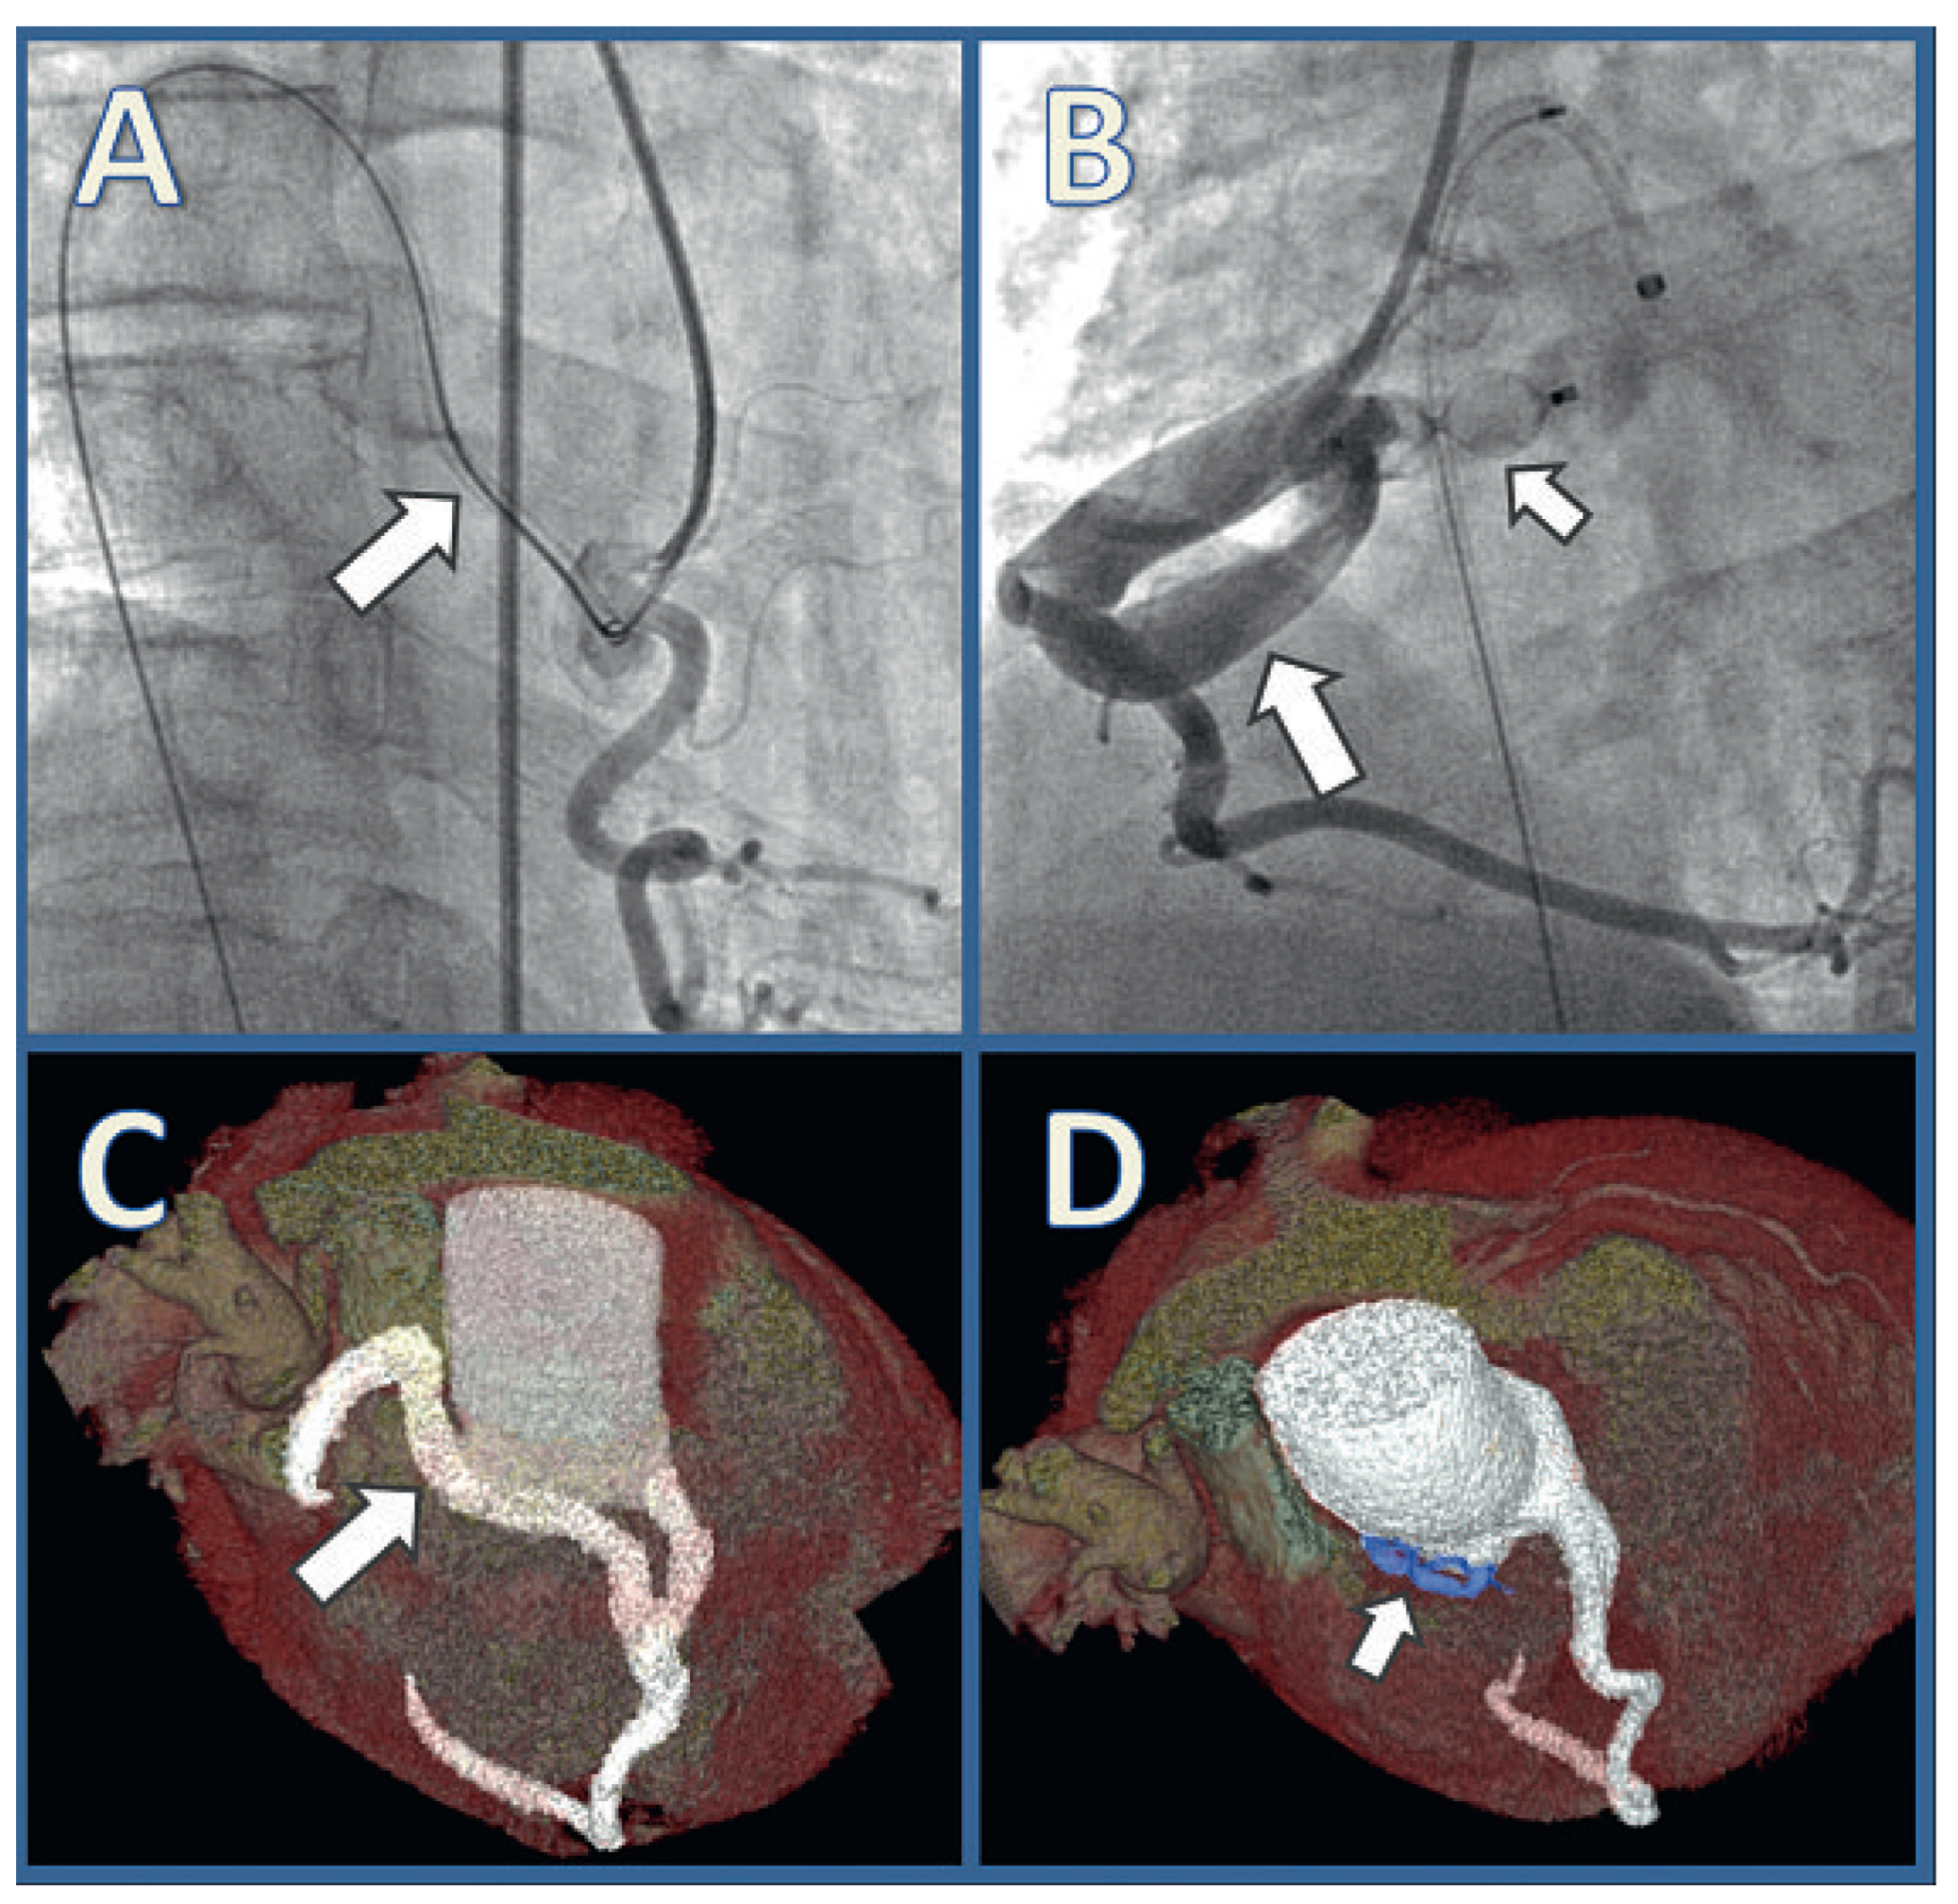

Transcatheter Closure of a Large Right Coronary Artery Fistula in a Patient with Bacterial Endocarditis